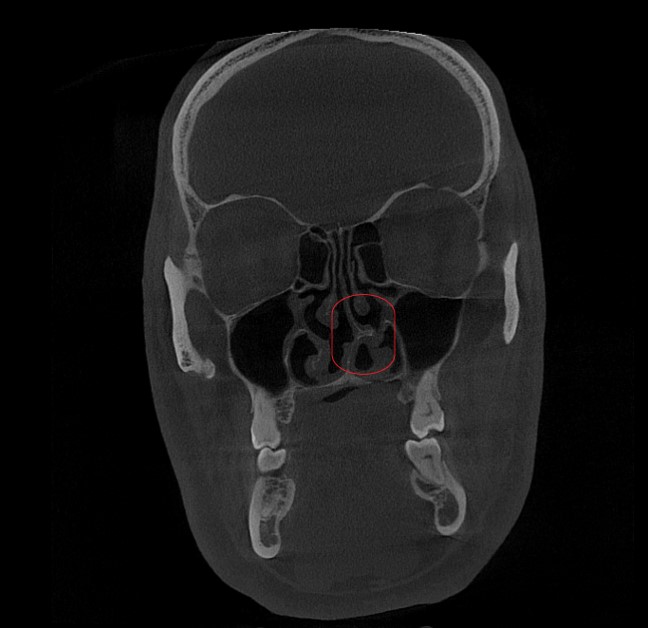

КТ (компьютерная томография) околоносовых пазух. Подтвердила наличие анатомического затруднения носового дыхания - искривление носовой перегородки и увеличение (гипертрофию) нижних носовых раковин.